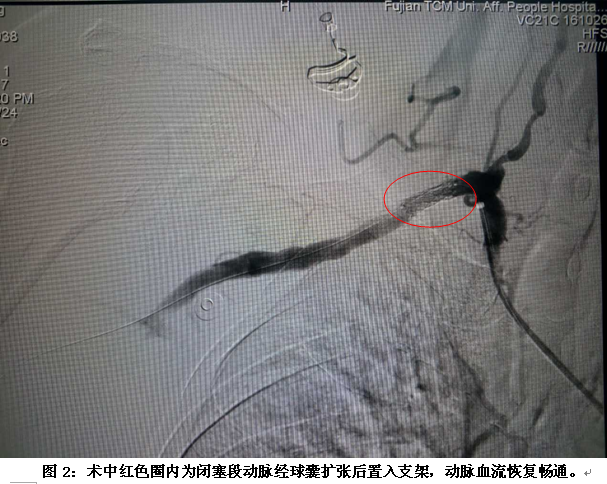

五年前李老伯出現(xiàn)右上肢麻木,經(jīng)檢查發(fā)現(xiàn)右上肢血壓較左上肢低,脈壓差>50mmHg,右上肢最低收縮壓僅60mmHg。2個月前,李老伯右上肢麻木加重,伴見右手無力、持筷困難、右手皮溫冰冷、感覺遲鈍、靜息痛、右手橈動脈無法觸及搏動。入院前1天,李老伯上述癥狀加重,就診我院。查右上肢動脈CTA示:右上肢動脈部分狹窄、閉塞(圖1)??紤]李老伯合并高血壓病、2型糖尿病、慢性心功能不全、慢性貧血(術(shù)前血紅蛋白僅68.0g/l)、腦梗死等,給手術(shù)增加了較大難度。經(jīng)完善術(shù)前會診及科內(nèi)充分討論后,決定給予行微創(chuàng)介入治療。于2017年9月4日于局部浸潤麻醉下行“經(jīng)皮右上肢動脈DSA+閉塞段血管腔內(nèi)治療+右腋動脈置管溶栓術(shù)”(圖2、3)。術(shù)后李老伯右上肢疼痛消失,麻木、無力癥狀明顯改善,右上肢肱動脈、橈動脈搏動好,膚溫如常。李老伯順利在術(shù)后第3天出院。